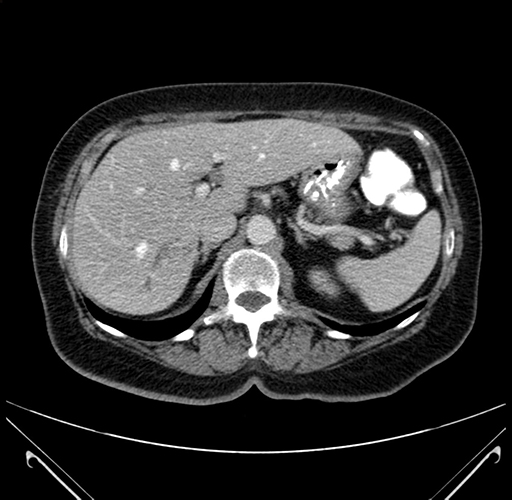

Pre-Chemo: Axial Venous

Axial Venous